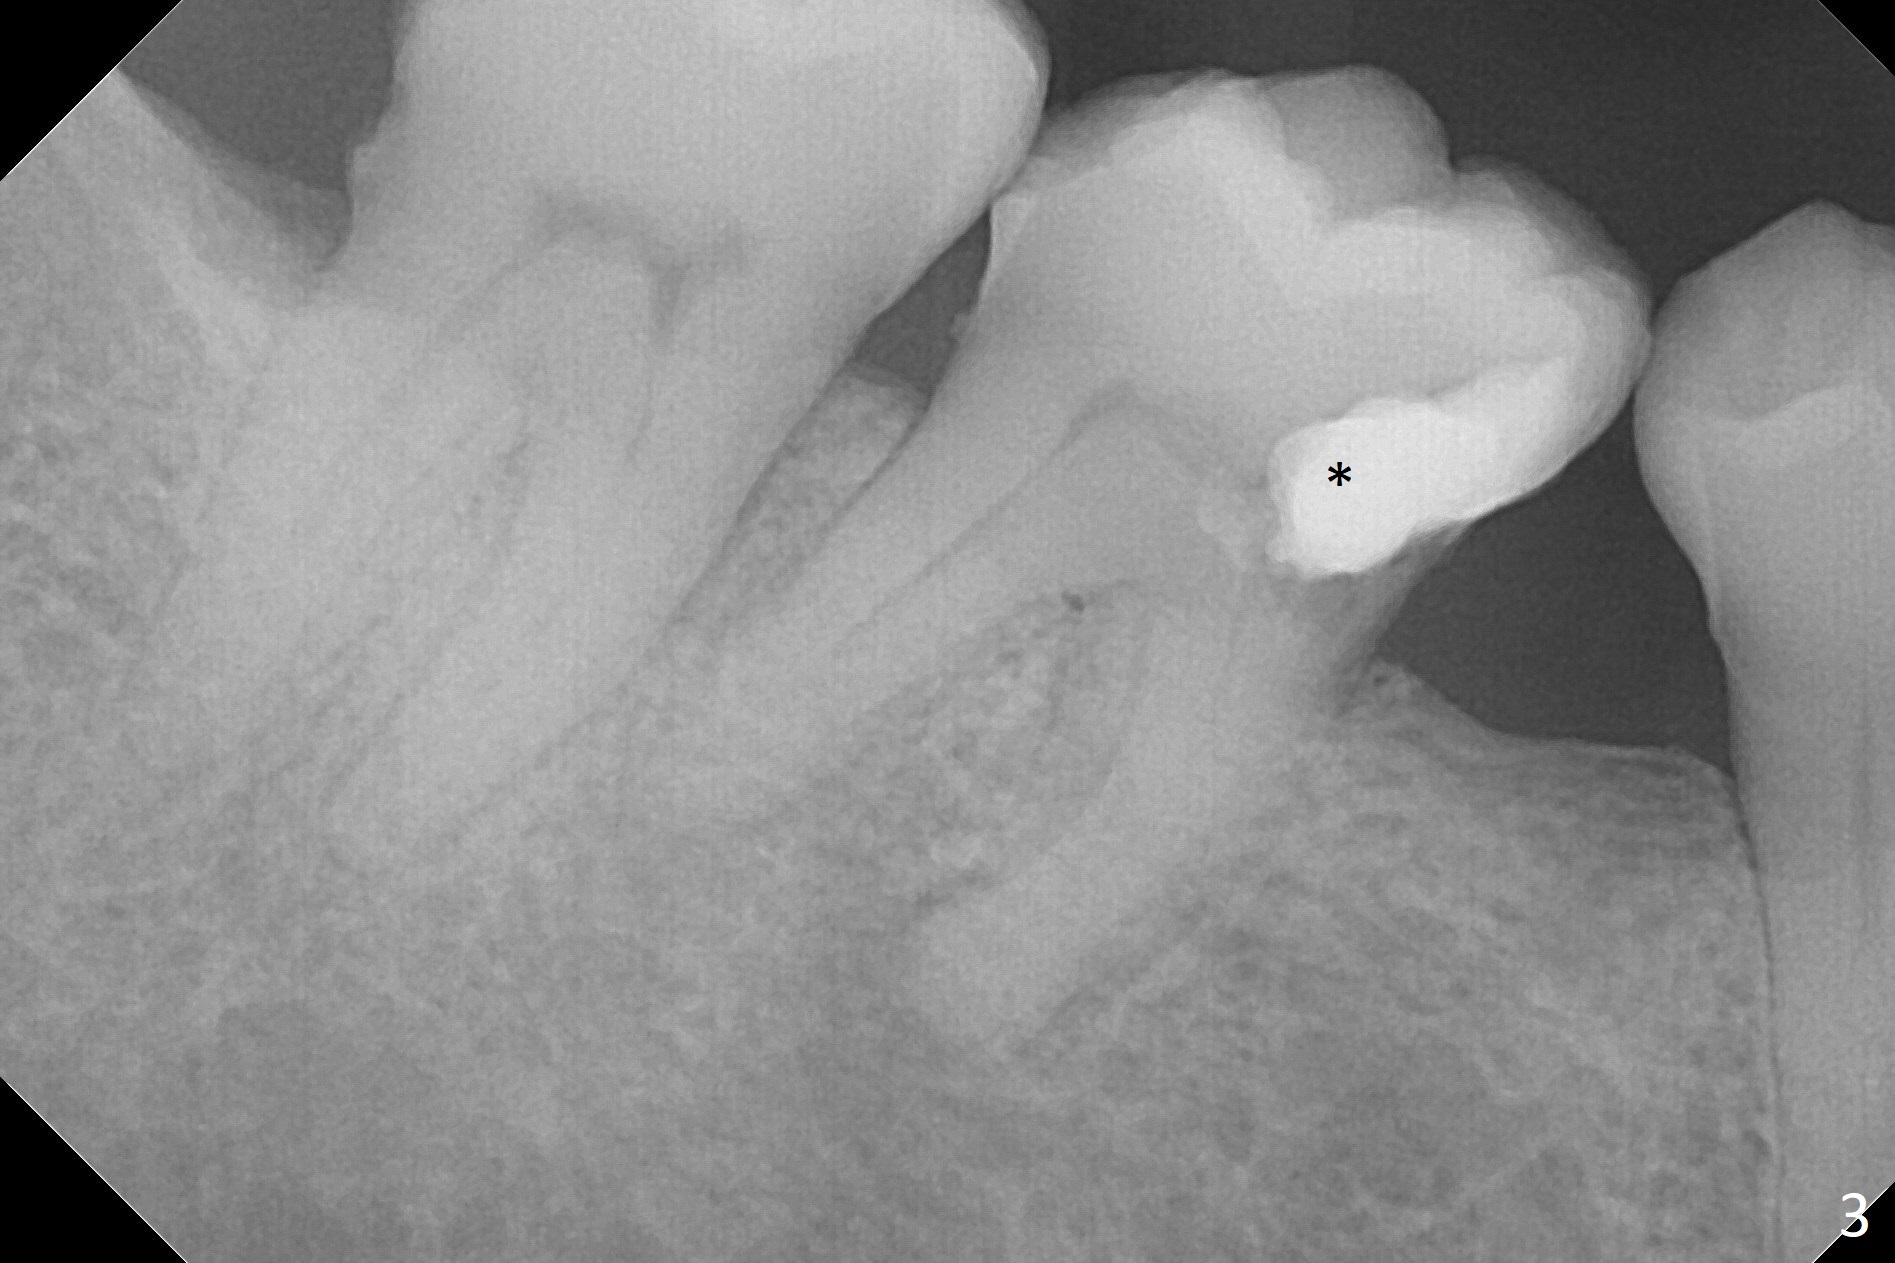

A 58-year-old man has history of temporomandibular joint disorder as related to severe occlusal breakdown and missing tooth #18 (Fig.1,4). The tooth #29 is also missing; the tooth #30 has shifted and tilted mesial. Severe pain develops at #30 two years after MOL composite (Fig.3). The patient insists on extraction and implant, although pulpotomy has been done to alleviate the pain. Although there is sufficient bone height, IS implants will be used because of primary stability and apparent better implant/abutment binding as compared to IBS (with tendency of screw loosening). Osteotomy will be initiated in the mesial socket at #30. Measure the whole length of drills. Find 17-8 mm mark, which will be used as soft tissue landmark.

Since the bone density at #30 is low, underprepare the site #18. The depth will be 15 mm with flapless technique. Prepare Magic Split and Expanders.